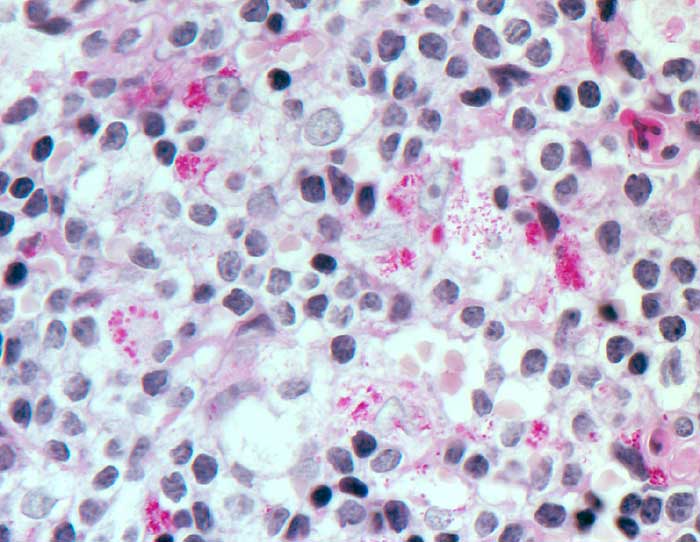

PathoPic – image database / PathoPic ID 6449 - Morbus Whipple

Morbus Whipple

Entzündung infektiös

Lymphknoten, mediastinal

Geschwollene Histiozyten enthalten PAS positive Partikel.

Morphologisch lässt sich die Erkrankung vor allem im Gastrointestinaltrakt, in den mesenterialen Lymphknoten, im Herz und im Zentralnervensystem nachweisen. Beweisend ist die Dünndarmbiopsie, welche eine Akkumulation von Makrophagen zeigt. Diese enthalten Diastase-PAS positive sichelförmige Partikel, die elektronenmikroskopisch 1.5 bis 2.5 Mikrometer grosse Bakterien enthalten. Diese Bakterien lassen sich auch in intestinalen Epithelien, lymphatischen und kapillären Endothelzellen, glatten Muskelzellen und neutrophilen Granulozyten nachweisen. Es können sich auch sarkoidoseähnliche Granulome ausbilden, die nur wenige Erreger enthalten. Tropheryma Whippelii gehört zu den Aktinomyceten. PAS positive Bakterien persistieren lange nach Verschwinden der Symptome. Das Bakterium kann mit PCR nachgewiesen werden. Mykobakterien sollten mit der Ziehl Neelsen Färbung ausgeschlossen werden.

Histologie

630